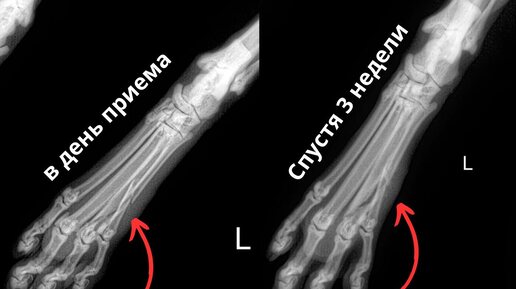

На приёме у Семернёва Егора Владимировича была 13-летняя кошка Буся. ✅Жалобы хозяина: хромота. Выполнена рентгенография, по результатам которой был обнаружен перелом 3 и 4 костей плюсны. Доктор установил, что перелом стабилен, так как кошка может опираться на 2 оставшиеся кости. Поэтому для ускорения заживления перелома было рекомендовано лишь ограничить питомцу подвижность (клеточное содержание) на определенный срок. Спустя почти 3 недели, проведя контрольную рентгенографию, доктор отметил,...